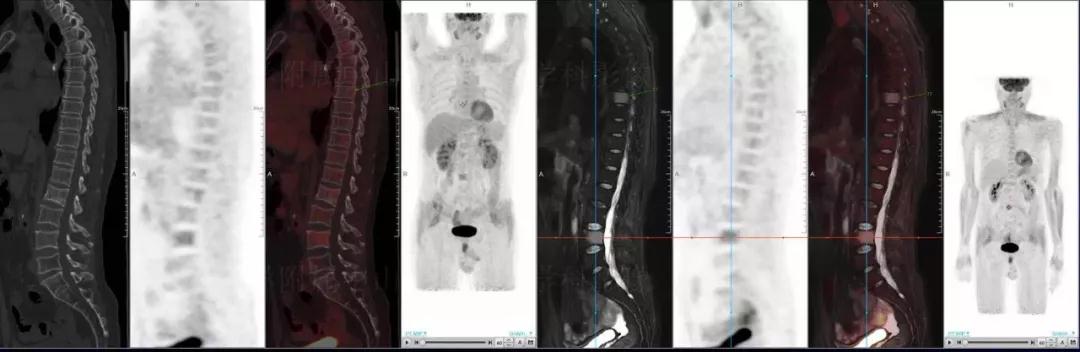

多發(fā)性骨髓瘤

中山醫(yī)院核醫(yī)學(xué)科基于聯(lián)影“時(shí)空一體”超清TOF PET/MR的融合顯像優(yōu)勢(shì),進(jìn)行了大量的臨床掃描,發(fā)現(xiàn)多例由MGUS向多發(fā)性骨髓瘤轉(zhuǎn)變,并從中總結(jié)出了一定的共同征象,未來可能實(shí)現(xiàn)多發(fā)性骨髓瘤的早期篩查。此外,PET/MR在多發(fā)性骨髓瘤的療效評(píng)估方面,也存在顯著優(yōu)勢(shì)。

(男性,53歲。確診多發(fā)性骨髓瘤10月。經(jīng)過7周期VCD方案化療后,現(xiàn)行療效評(píng)價(jià)。)